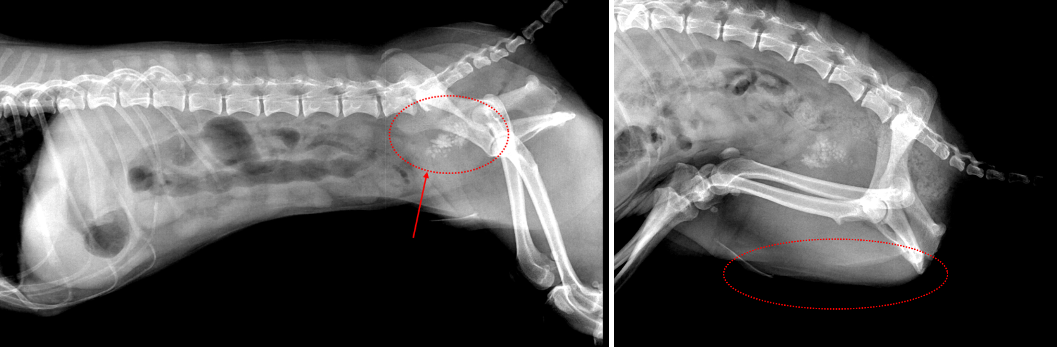

췌장염 검사를 진행하던 중

엑스레이에서

다량의 방광결석이 확인이 되었습니다.

말티즈 아이의 경우 수컷으로

결석이 요도로 내려가

막힐 위험이 있기때문에

빠른 시일의 수술이 필요한 아이였습니다.